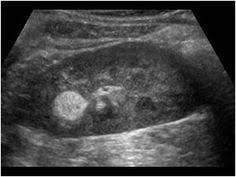

Renal Metastases With A Well Visible Right Renal Mass Diagnostic Medical Sonography Vascular Ultrasound Ultrasound Sonography

Renal Metastases With A Well Visible Right Renal Mass Diagnostic Medical Sonography Vascular Ultrasound Ultrasound Sonography from www.pinterest.com